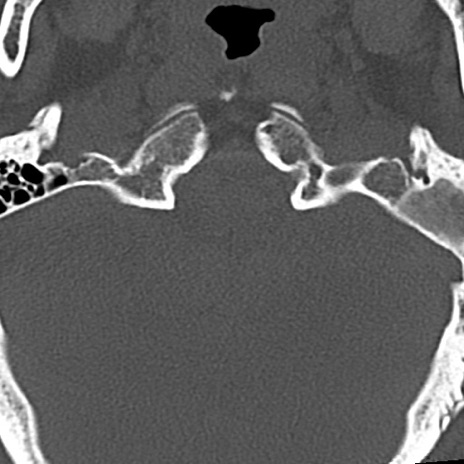

頚椎CT

横断像